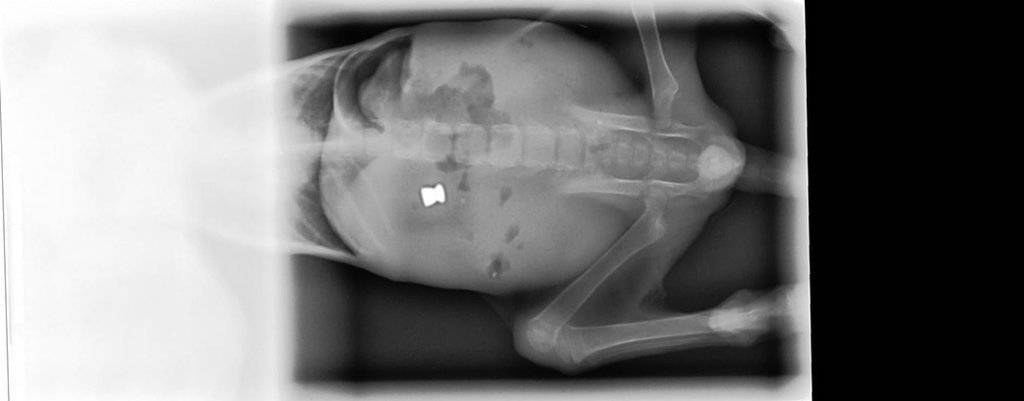

Ens van portar un gat al Centre Veterinari d'Almacelles i vam comprovar que estava desnodrit (pesava 340 grams) i que no tenia mobilitat al terç posterior, afectant les extremitats posteriors i cua. En fer unes radiografies vam comprovar que li havien disparat amb una escopeta de balins i que un balí de copa li havia provocat una lesió a la columna vertebral.

El balí el vam treure aquesta setmana, ja que, a causa de una úlcera que s'ha fet en un ull, hem hagut d'operar-lo per intentar salvar-li l'ull, i hem aprofitat per treure el balí que es palpava perfectament a l'abdomen, darrere de l'última costella, a prop de la columna.